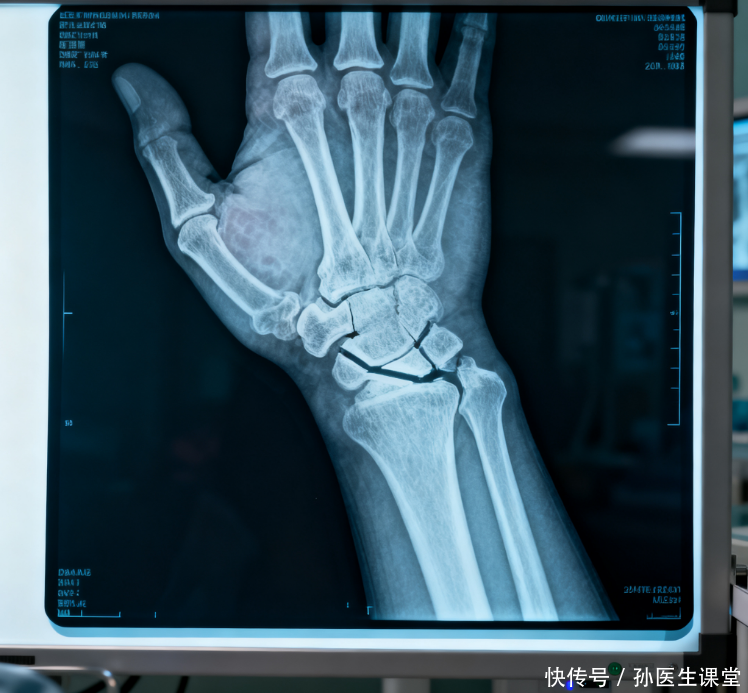

我国骨折发病率攀升,医生:这3个习惯伤害骨骼,预防从现在开始

随着社会的进步,骨折似乎逐渐成为了一种“常见病”,尤其是在老年人群体中,然而,近年来,我国年轻人的骨折发病率也在悄然上升,尤其是那些久坐、缺乏锻炼、饮食不健康的现代人群,似乎比以前更容易遭遇骨折的困扰,那么究竟是什么原因导致骨折的发生率逐年攀升?我们该如何从日常生活中做出改变,避免骨骼受损?